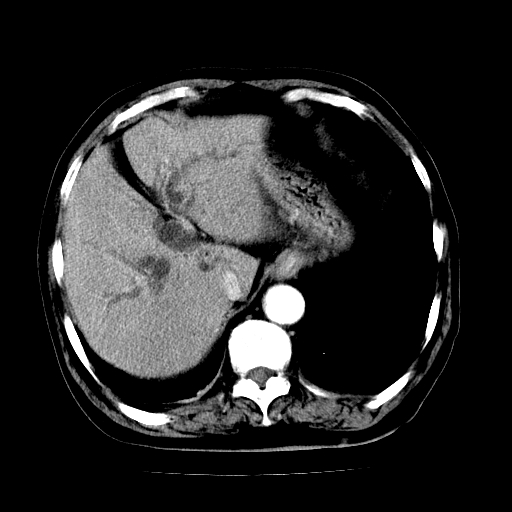

男,71岁,皮肤黄染四天。

肝内外胆管及胆总管上段扩张,考虑为梗阻所致,建议mrcp检查。

胰腺上端胆总管内见软组织影,强化不明显,结合临床,还是考虑低位梗阻性黄疸,胆总管癌可能性大